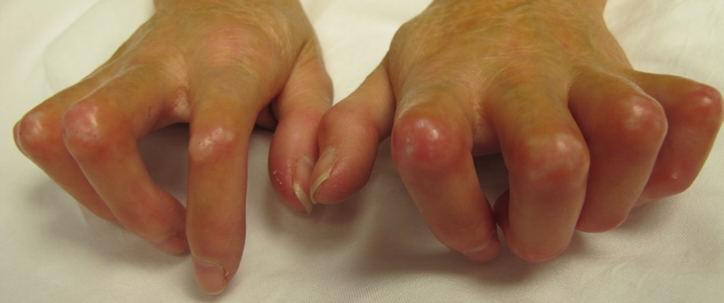

Gout

- Gouty tophi in finger joints

- Gouty tophi: Elbows, wrists

- Tophi in big toe (75% of cases)

- Tophi in Achilles tendon